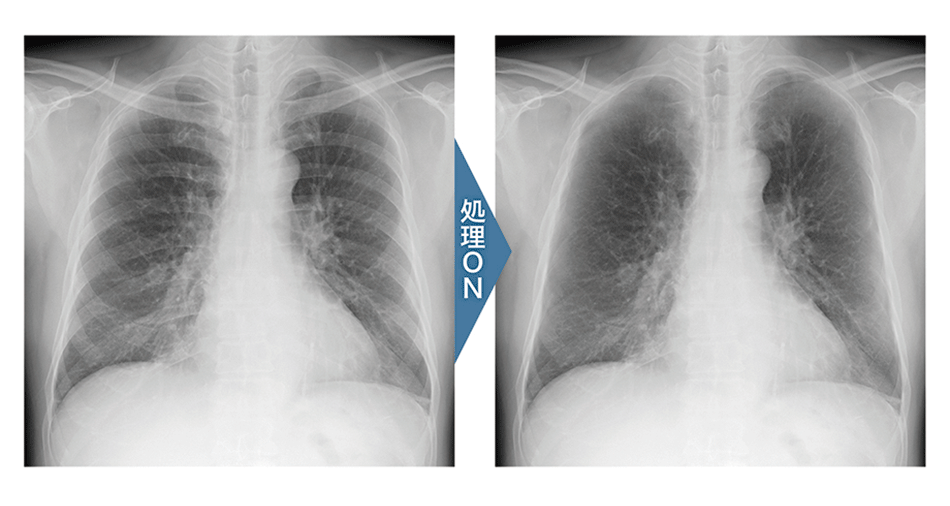

画像全体の描出とコントラスト維持の両立

改良されたダイナミックレンジ圧縮の処理と、新規のLUT(階調カーブ)により、低線量域から高線量域まで各構造物を分離良く表現し、白トビ・黒ツブレを起こすことなく画像全体を自然なままに描出することで立体感のある画像を提供します。

Bone Suppression処理(胸部骨減弱処理)

医師が頭の中でイメージしている「鎖骨 / 肋骨の減弱像」 を可視化することにより、読影を支援。 鎖骨・肋骨部分に隠れた病変の見落とし防止に貢献します。